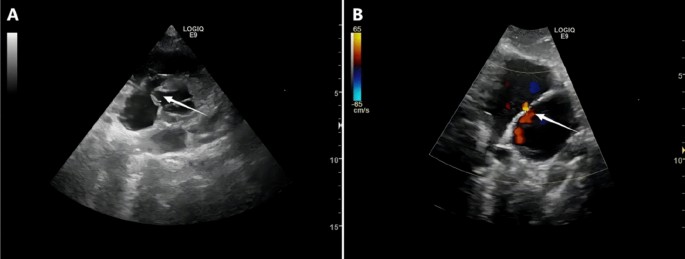

Microtia patients with identified ECG abnormalities or clinical concerns underwent further cardiac evaluation, which may have included echocardiography (GE LOGIQ E11, California, USA) or additional imaging studies, as deemed necessary based on the initial ECG findings.

The further examinations were done in some microtia patients with abnormal ECG. The typical cases were shown in Figs. 3 and 4.